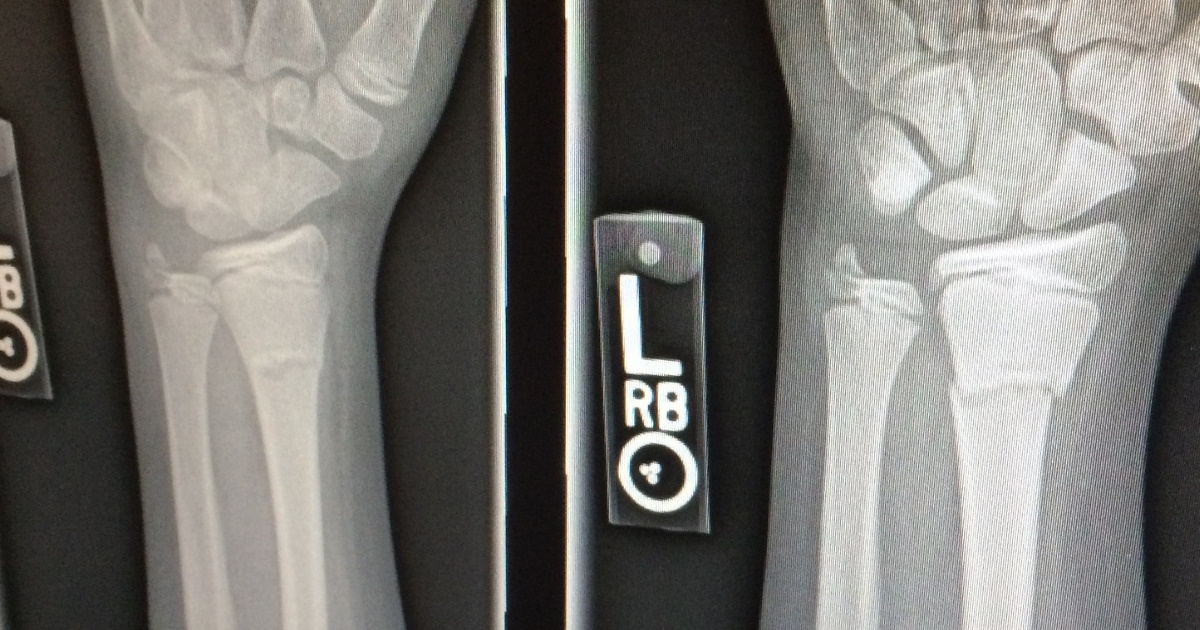

Daraufhin war es in diesem Winter soweit: drei Ermüdungsbrüche

Kernspin hat gezeigt, dass der Knochen wirklich „durch“ war und normales Gehen deshalb nicht mehr möglich – nur noch Humpeln